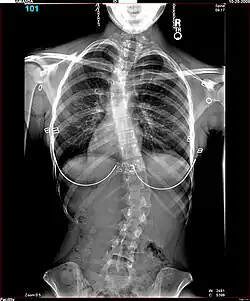

Polio patients would sometimes develop scoliosis, a condition where the spine becomes curved laterally (from side to side).[5] Harrington realised that existing treatments for scoliosis, which relied heavily on physical therapy, were inappropriate for patients paralysed by polio, and began to research new treatments. An early method he tried for scoliotic polio patients was manual correction of the scoliotic deformity at the time of surgery, and internal fixation of each facet. There were some benefits to this treatment but Harrington found that the fixation would not hold.[4] The hooks and threaded rods used would corrode and break, causing curvature to return to the spine. Two patients of this procedure died.[5]

The Harrington Rod, or Harrington implant, is a device for the straightening of the spine inside the body, designed by Paul Harrington. The device consists of a stainless steel rod, attached to the spine at the top and bottom of the curve with hooks. Attached ratchets are then tightened to distract or straighten the spine. Following surgery to insert the rod, the patient wears a postoperative plaster cast or brace for a few months, until vertebral fusion has occurred, after which the cast or brace is removed.[5]